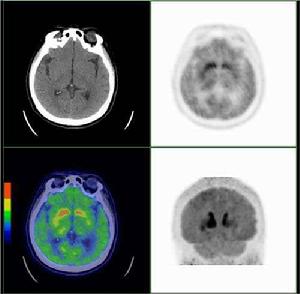

多巴胺D1受體顯像劑可用於研究腦內多巴胺受體的分布及其區域濃度 的,川放射性核素標記的i},受體配體,稱為D‘受體顯像劑 用放射性核素標記的r},受體的選擇性激動劑或拮抗荊及其 衍生物可川於n〕受體顯像劑,如’iC}iRF或123}}標記的n,選 擇性拮抗劑;},C;H23390.